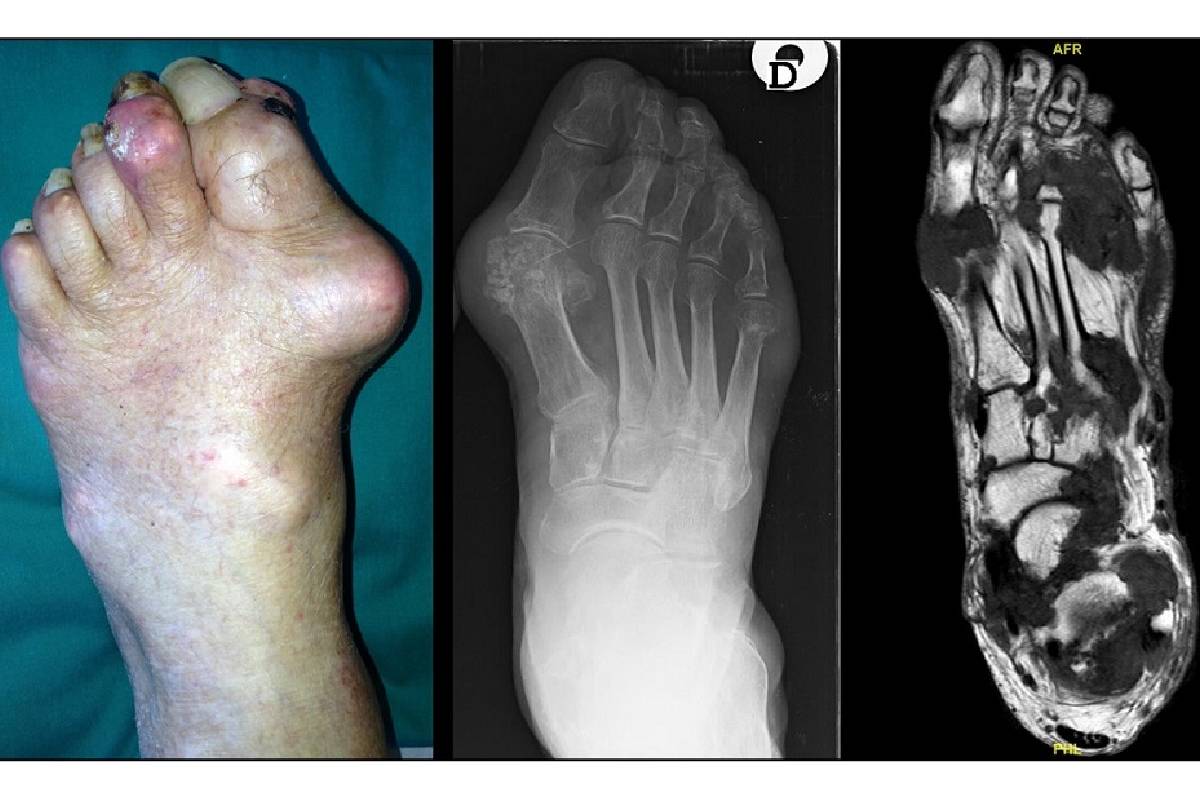

6. نقرس پا

نقرس معمولاً انگشت بزرگ پا را درگیر میکند، اما میتواند به سایر قسمتها گسترش یابد. این بیماری با درد شدید، تورم و قرمزی همراه است و اغلب شبها شروع میشود.

برای تشخیص دقیق علت درد روی پا، پزشک ابتدا معاینه فیزیکی انجام میدهد و به دنبال علائم مانند تورم یا حساسیت میگردد. تصویربرداری مانند اشعه ایکس برای بررسی شکستگیها مفید است. در موارد پیچیده، ام آر آی یا سی تی اسکن برای دیدن بافتهای نرم استفاده میشود. آزمایش خون میتواند عفونت یا بیماریهایی مانند نقرس را شناسایی کند. گاهی نوار عصب و عضله یا بیوپسی لازم است تا علت دقیق مشخص شود.